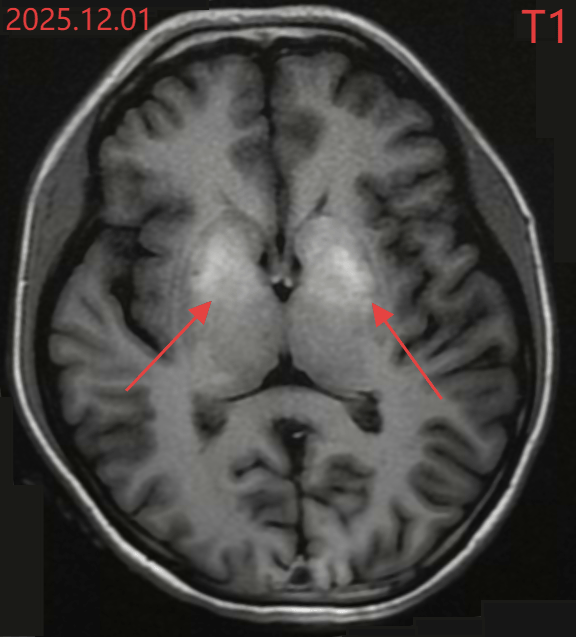

小文的颅脑MR结果

进一步的检查更令人震惊:糖化血红蛋白17.7%(正常应在6.5%以下),这意味着她的血糖在很长一段时间内都处于“失控”状态。颅脑MR显示,她大脑深处控制运动的基底节区域已经出现异常信号——这是长期高血糖对大脑的“灼伤”。